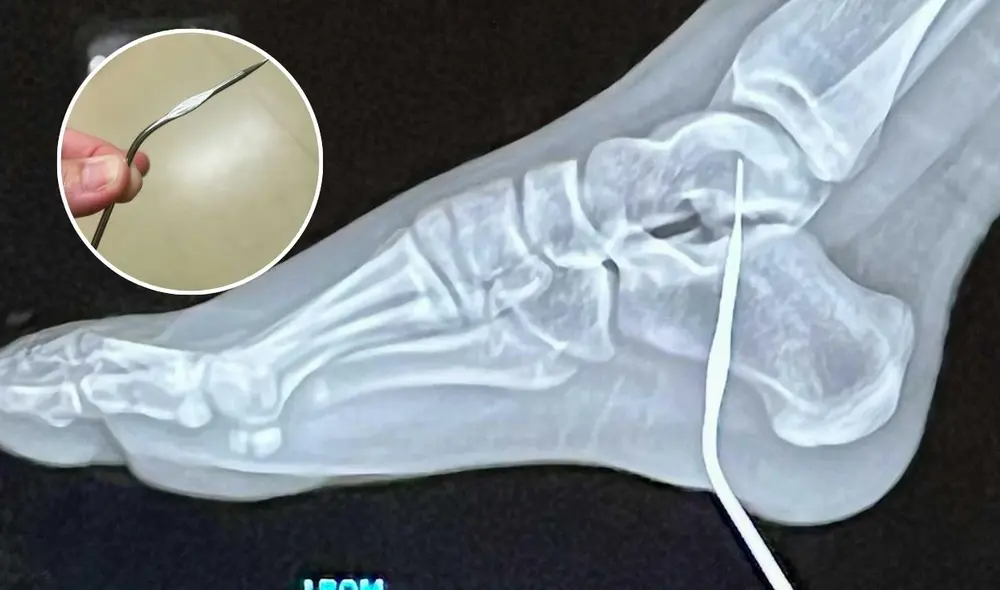

El hospital en California al que fue llevada Georgia fue el escenario de una sorpresa para los médicos que atendieron su caso. Después de realizarle una radiografía, los médicos confirmaron que la aguja había quedado incrustada profundamente, pero afortunadamente no había afectado estructuras vitales como huesos, nervios o músculos. "Fue un accidente extremadamente inusual", comentó Ashley.

El personal médico mostró gran asombro al conocer los detalles del caso, comentando que nunca habían enfrentado una situación similar. “No podían creer lo que veían", explicó la madre de la niña. El hecho de que la aguja se haya alojado en un área tan sensible sin causar daños severos es una bendición, aunque el incidente demostró lo peligroso que puede ser el desorden en el hogar. Maggie, la hermana menor de Georgia, había comenzado a aprender crochet, pero sin la supervisión adecuada, había dejado las herramientas peligrosas por todo el suelo de la casa.